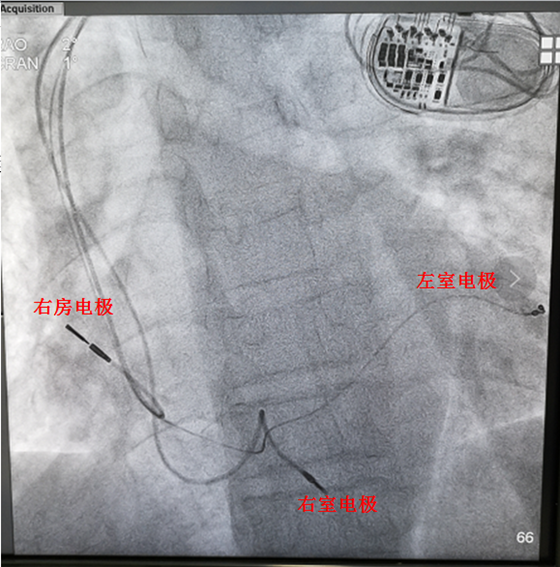

4月8日,湘雅常德医院彭道地主任与中南大学湘雅医院李振宇博士、范爱德副主任医师及起搏器专业技术人员共同完成CRT植入手术。于病人局麻后,穿刺左锁骨下静脉,留置导丝,于左上胸作一长约4.0cm横行切口,逐层分离至胸大肌筋膜,作一肌内囊袋。在导丝引导下,送左室电极至左室侧静脉,心室电极入右室心尖部,心房电极入右房心耳部,将脉冲发生器(起搏器)置入囊袋并缝合。最后经专业技术工程师指导下测定起搏器参数良好。手术历时两个小时,术中患者无明显不适。

术后患者诉胸闷、气短明显好转,夜间咳嗽消失,双下肢不肿,复查心电图:QRS宽度120ms(较入院心电图QRS 宽度明显缩窄),心脏超声有好转:心脏瓣膜反流明显减轻,肺动脉压力恢复正常范围。